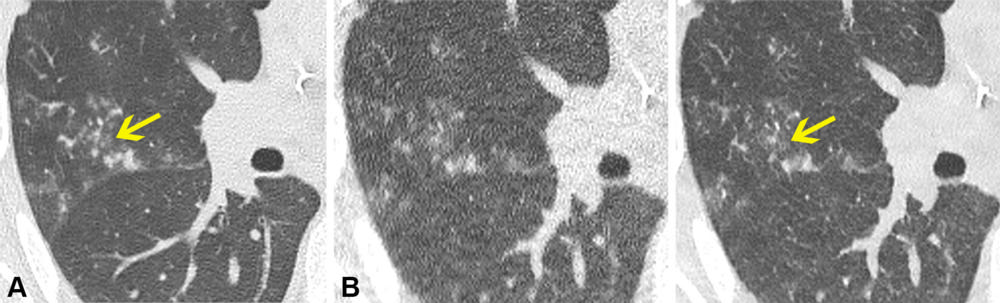

Figure 5. Axial noncontrast chest CT lung window images in a 70-year-old male participant. (A) Normal-dose CT, (B) ultra-low-dose CT (ULDCT), and (C) denoised ULDCT images show tree-in-bud opacities (yellow arrow). The tree-in-bud opacities can be observed on normal-dose CT image. However, due to the increased image noise at ULDCT, the linear branching pattern was missed and classified incorrectly by both readers as nodules with no tree-in-bud opacities. Denoised ULDCT allowed better appreciation of centrilobular nodules with a linear branching pattern, and the image was classified correctly as positive for tree-in-bud opacities.